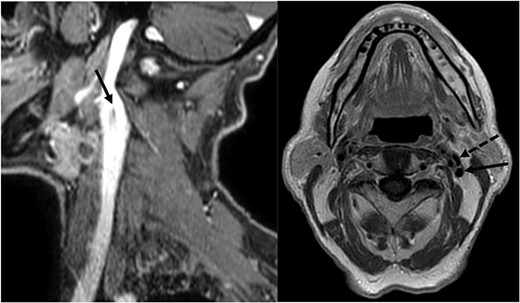

A 78-year-old man with a follow-up PET for a Type B mantle cell lymphoma finding of uptake in in the epiglottis and left laterocervical region is reported here. The patient was diagnosed with squamous cell carcinoma (SCC) after fine needle aspiration of an adenopathy at Level II. His workup included an MRI of the neck with contrast enhancement, which revealed laterocervical lymphadenopathy (bilateral level IIa and left Level III with the biggest adenopathy with maximum diameter of 12 × 12 mm) and thickening of the epiglottis extended at the floor of the left vallecula. No mention was made of an IJV abnormality in the report even though it was noticed during the preoperative evaluation by the surgeon (Fig. 1). The fibroendoscopic evaluation of the neck showed an asymmetry of the epiglottis with the presence of vegetating tissue at the level of the left lingual border of the epiglottis, preserved motility of the vocal cords, and normal breathing space. The patient’s clinical stadiation was cT2 N2c M0. The multidisciplinary meeting indicated an endoscopic partial laryngectomy and bilateral laterocervical dissection. The cervical lymph node dissection on the left side discovered a duplication of the IJV which resulted dilated in comparison to the IJV on the right side. The SAN passed medially to the anterior vein and laterally to the posterior vein. Both the IJV and the SAN were preserved during the procedure (Fig. 2).

MRI showing the fenestration of the IJV; left image: sagittal section showing the fenestration (arrowhead) of the left IJV; right image: axial section showing the anterior (dotted arrowhead) and the posterior (arrowhead) part of the fenestrated IJV.